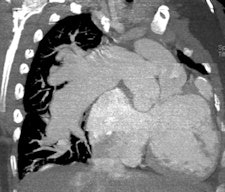

MDCT using a low radiation dose protocol is the best diagnostic tool for assessing the central airway, cardiovascular and mediastinal abnormalities, and the lung parenchyma in children, and the relevant information can be acquired with a single-volumetric data set acquisition, she stated. Using thin-slice collimation acquisition with inherent isotropic resolution, the image data can be manipulated and reformatted to display 2D and 3D images with the same spatial resolution as the axial images, thus enhancing diagnostic accuracy and providing data that can be used in presurgical planning and patient management.